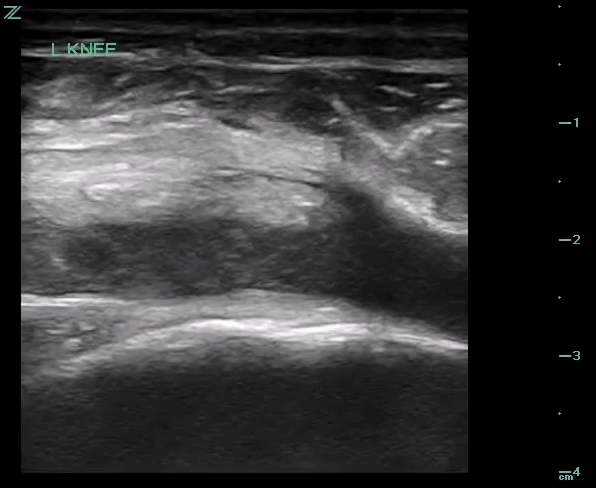

POCUS of the left knee was performed, which was concerning for a patellar tendon rupture and a joint effusion. (Figure 1 and Video 1) In addition, there was posterior acoustic shadowing obscuring part of the patellar tendon concerning for an avulsed bony fragment. (Figure 2) X-rays were performed, which confirmed the suspected diagnosis of a left tibial tubercle avulsion. (Figure 3) The patient was ultimately taken to the operating room for an Open Reduction and Internal Fixation (ORIF) by Orthopedic Surgery and discharged home the following day in a knee brace.

Video 1. Evaluation of the subpatellar space in transverse plane using compression that demonstrates swirl sign, suspicious for hemarthrosis or lipohemarthrosis.

In our case report, we successfully identified key features suggestive of tibial tubercle fractures: disruption of the patellar tendon, posterior acoustic shadowing of a bone fragment, and a large joint effusion. To perform knee ultrasound, the linear probe should be used and placed inferior to the patella in sagittal plane. The patellar tendon should be visualized in two planes, fanning through it completely (Video 1), and compared to the contralateral normal knee. (Figure 4) Abnormal findings suggestive of epiphyseal fractures include disruption of the tendon, an increased hypoechoic space adjacent to or posterior to the tendon (suggestive of either hemarthrosis or a hematoma), or a hypoechoic zone (ie, posterior acoustic shadowing due to an avulsed bony fragment).3,4